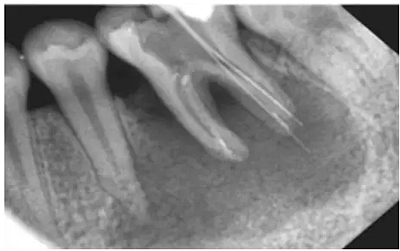

注:a.在鈣化細小/彎曲/形成臺階的根管,即使銼針未到狹窄區(qū),阻力也會明顯增大,導(dǎo)致感覺錯誤;b.在根尖周組織破壞嚴重(陰影部分),有痛感時,已明顯超出根管口。(如圖)

方法二:X光

采用X光拍片測量

優(yōu)點:能觀察牙的全貌,尤其是牙冠和牙根的解剖形態(tài),冠根關(guān)系以及牙根的大小、形態(tài)和位置

缺點:操作繁瑣、費事、射線污染

1) 三維結(jié)構(gòu)投射在二維平面上,因投射角度不一樣,數(shù)據(jù)容易出錯。

2)根尖孔不能體現(xiàn)在牙片上,而80%以上的根尖孔都不在牙齒根尖而是在側(cè)邊。

根尖開口在側(cè)邊時,X線片投射引起長度偏差錯誤。

根尖開口距離牙齒根尖距離越大,誤差越大,會引起嚴重超充。